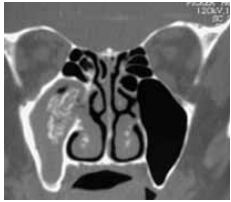

Paciente do gênero feminino, 45 anos, com queixa de obstrução nasal e rinorreia amarelada unilateral à direita há 7 meses traz a tomografia computadorizada de seios paranasais apresentada a seguir. À nasofibroscopia, observam-se edema e secreção purulenta em meato médio direito.

Frente a esse quadro, a conduta mais adequada é: